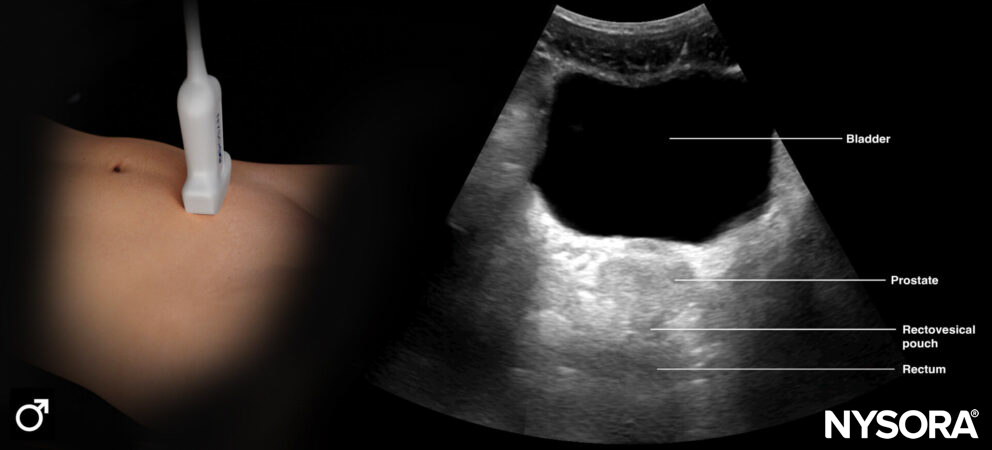

Transverse ultrasound view of the bladder (male).

Longitudinal Reverse Ultrasound Anatomy of the bladder (male).